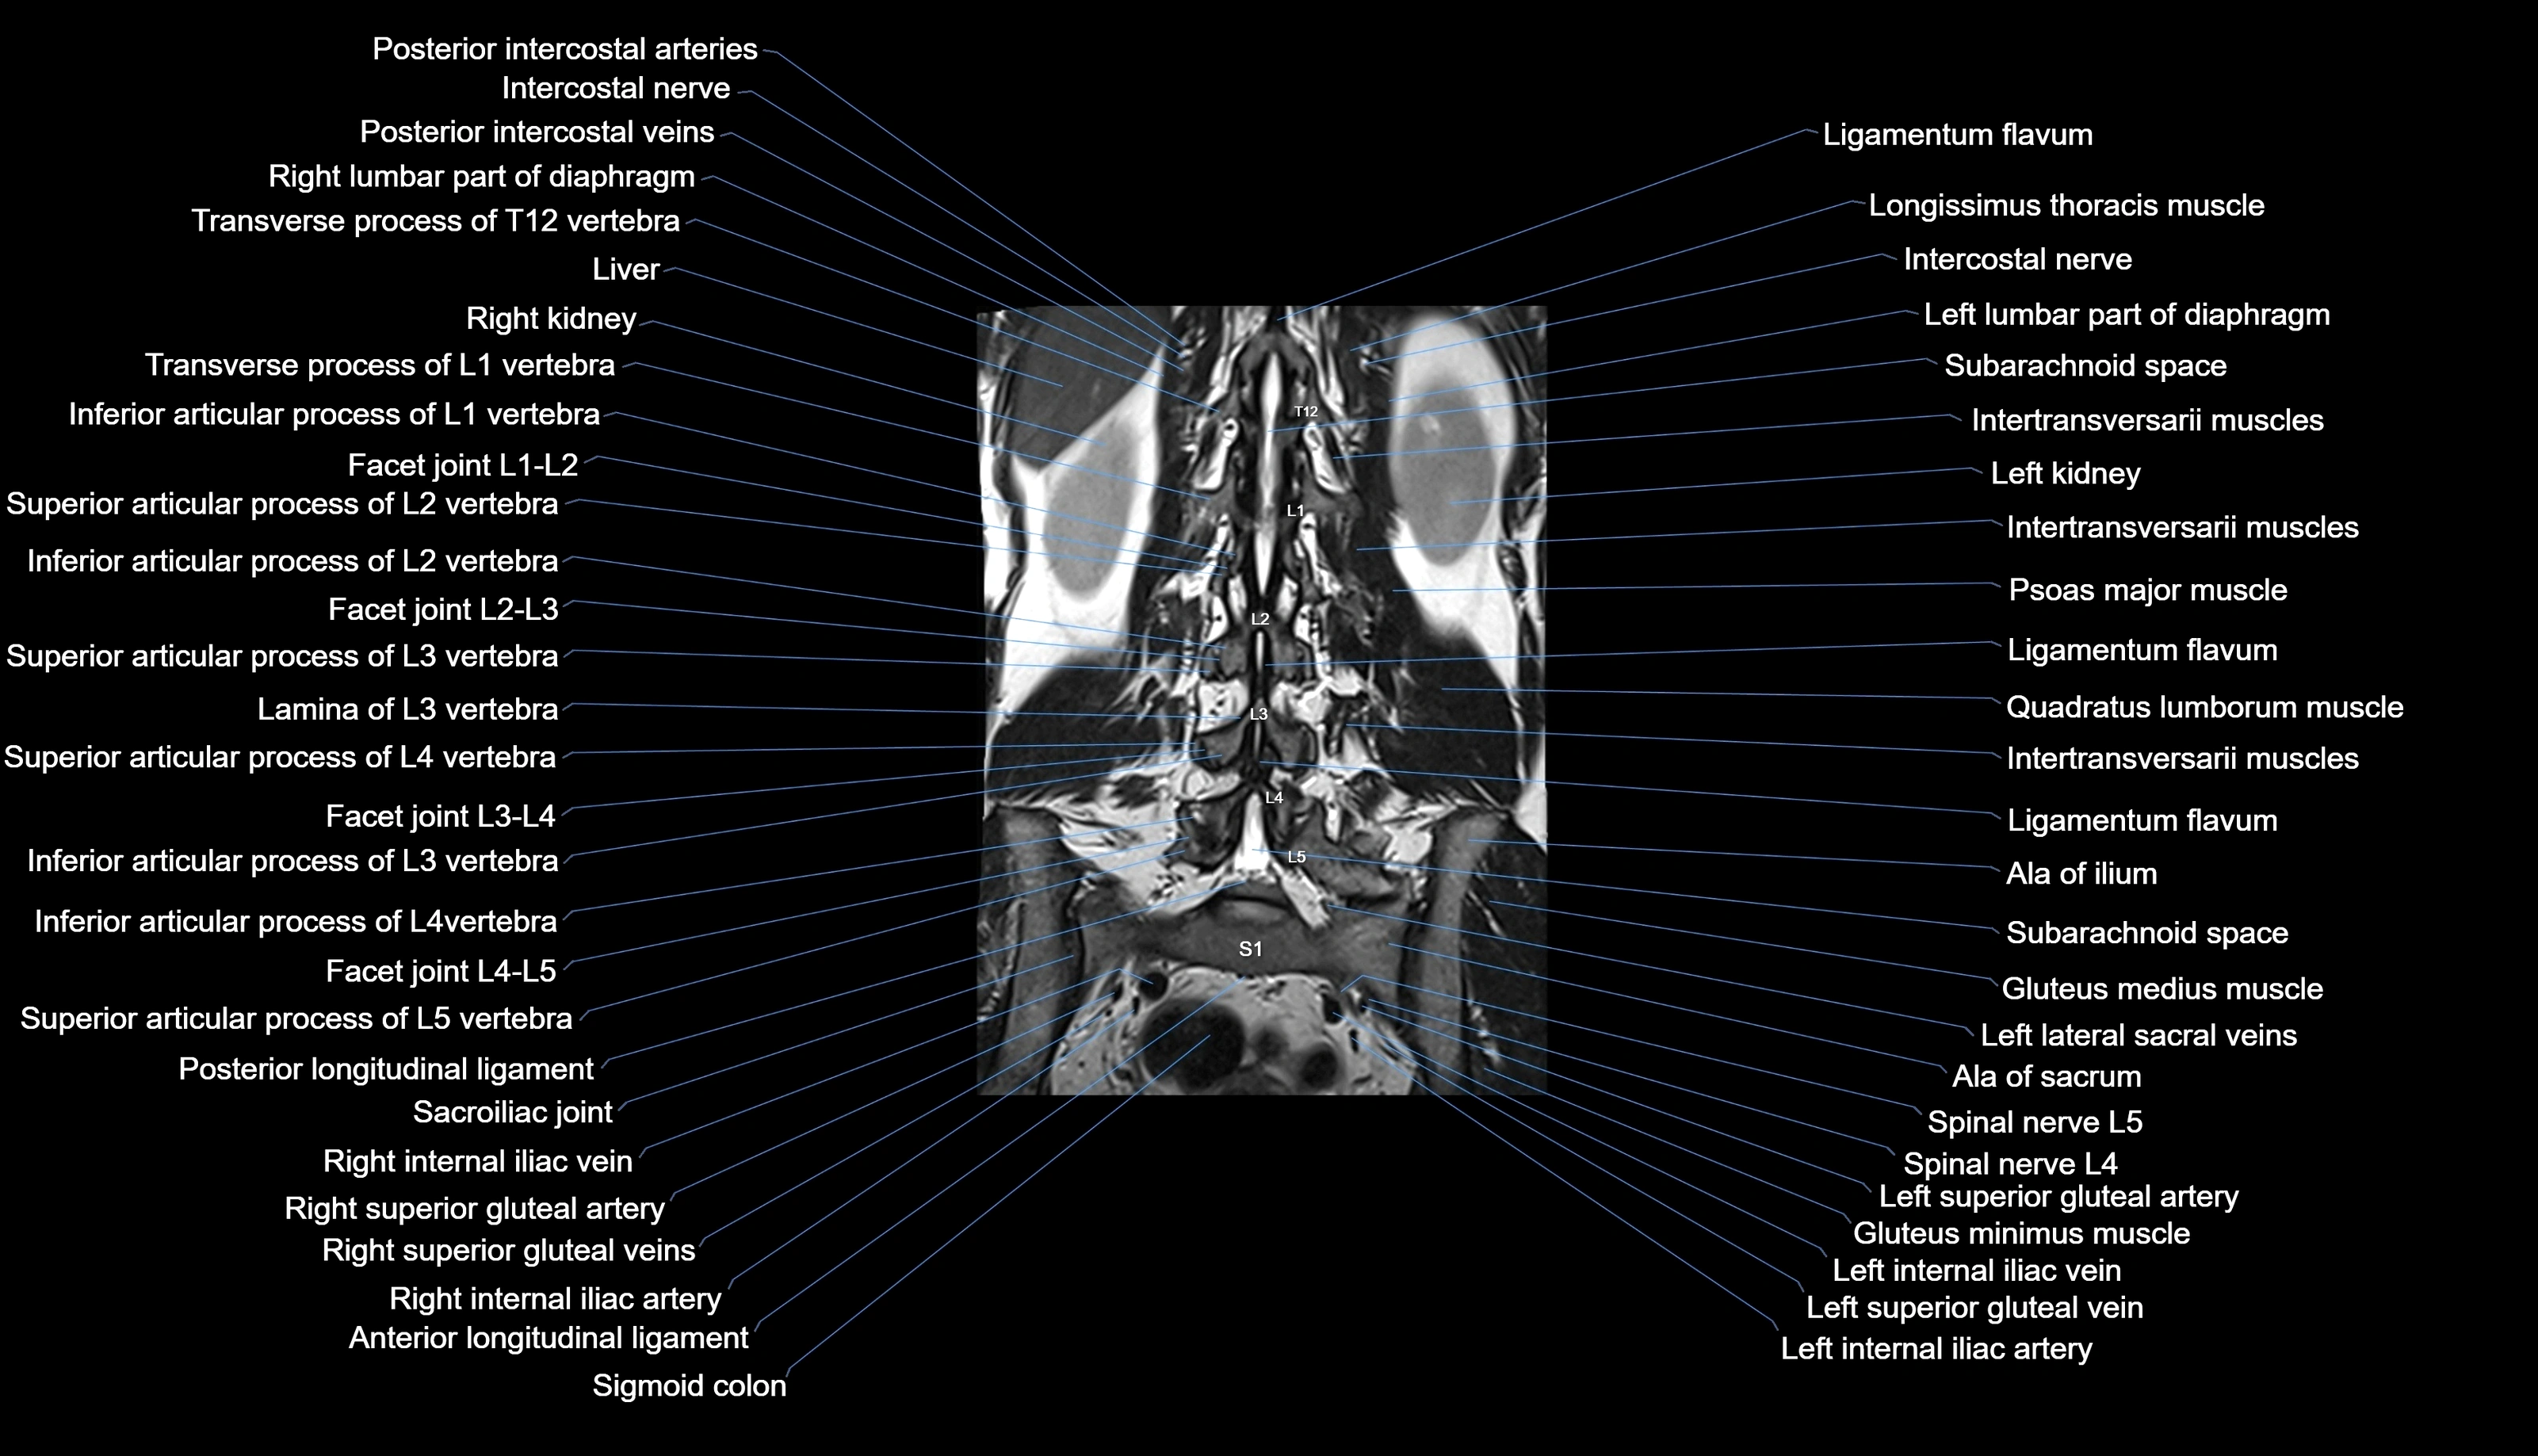

MRI images